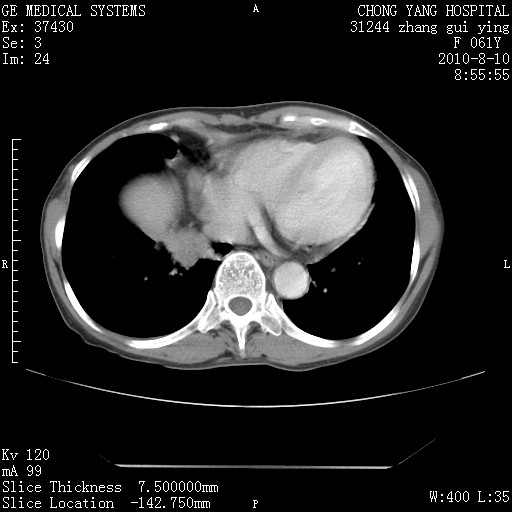

1、支持考虑右侧中央型肺癌伴右肺中叶节段性不张及下叶支气管黏液痰栓    2、左肺上叶舌段感染。

确切的说:1:右肺下叶中心型肺癌侵及中叶支气管并中叶不张,纵膈淋巴结转移。2:左肺舌叶炎症。3:右侧胸腔少量积液

块影平扫32hu,动静脉期62-70hu.

1:右肺下叶中心型肺癌侵及中叶支气管并中叶不张,纵膈淋巴结转移。2:左肺舌叶炎症。3:右侧胸腔少量积液。支持!

右肺下叶内基底段近膈不规则肿块,考虑右肺下叶周围型肺癌可能性大。